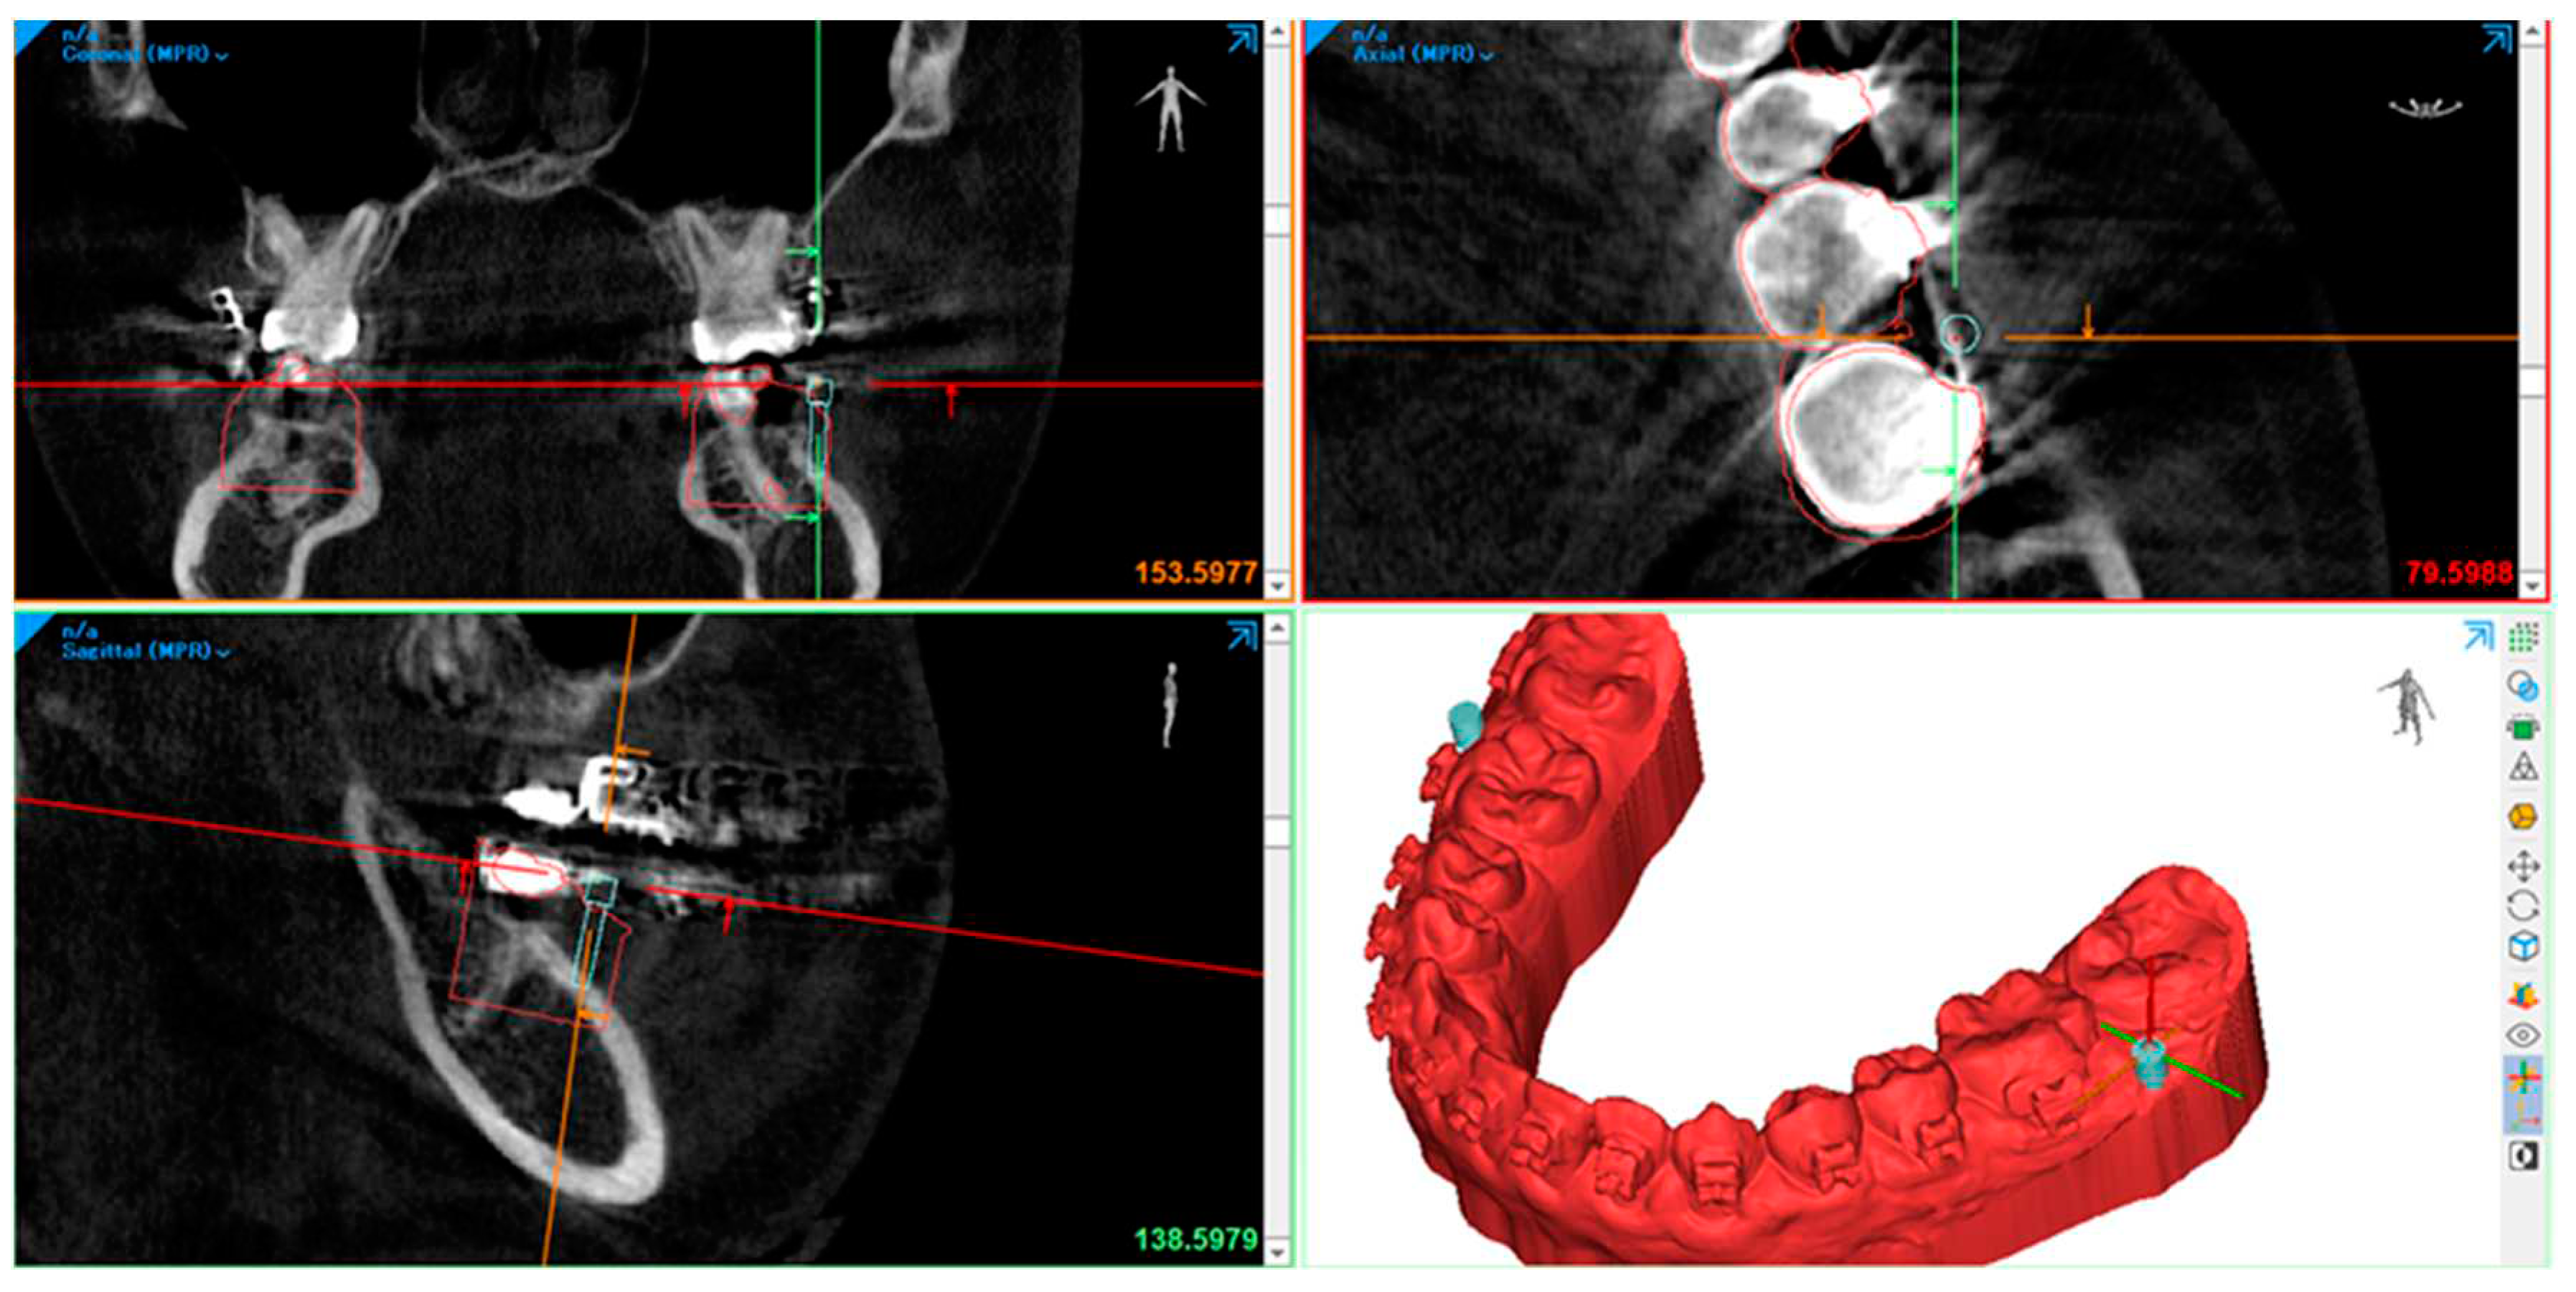

- We used an intra-oral scan for the SLT and a CBCT X-ray machine for the DICOM data to obtain a digital impression. afterward, we superimposed the STL and DICOM data using a commercialized application.

- The 3-Shape software completes the process of designing a surgical guide. By utilizing software, the diameter of the drilling bur and screw holder can be determined, ensuring no contact with the roots during the procedure. The 3-shape software simulates the screw placement within the bone's anatomic area. This simulation helps determine the tube design required for drilling and screw implantation.